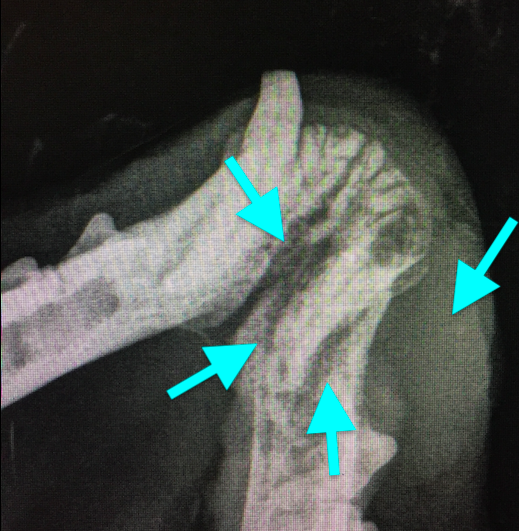

Резорбция зубов клинически часто проявляется отсутствием эмали и дентина зуба вблизи цементно-эмалевой границы, иногда она заполнена гиперплазированной десной и отмечается высокая кровоточивость при пальпации или зондировании этой области (фото 1).

Резорбтивные поражения могут локализоваться глубоко в альвеолах (поражается корень зуба), где происходит невоспалительная заместительная резорбция (корни зуба разрушаются и замещаются костью; фото 2).

При поражении коронки зуба имеется риск инфицирования зуба бактериями полости рта, что может привести к болезненному воспалению окружающих тканей (отек, боль, свищевые ходы, абсцедирование, остеомиелит; фото 3). Этиология этого заболевания у домашних кошек до сих пор не установлена. Существует несколько различных теорий, однако причинный фактор еще не определен.